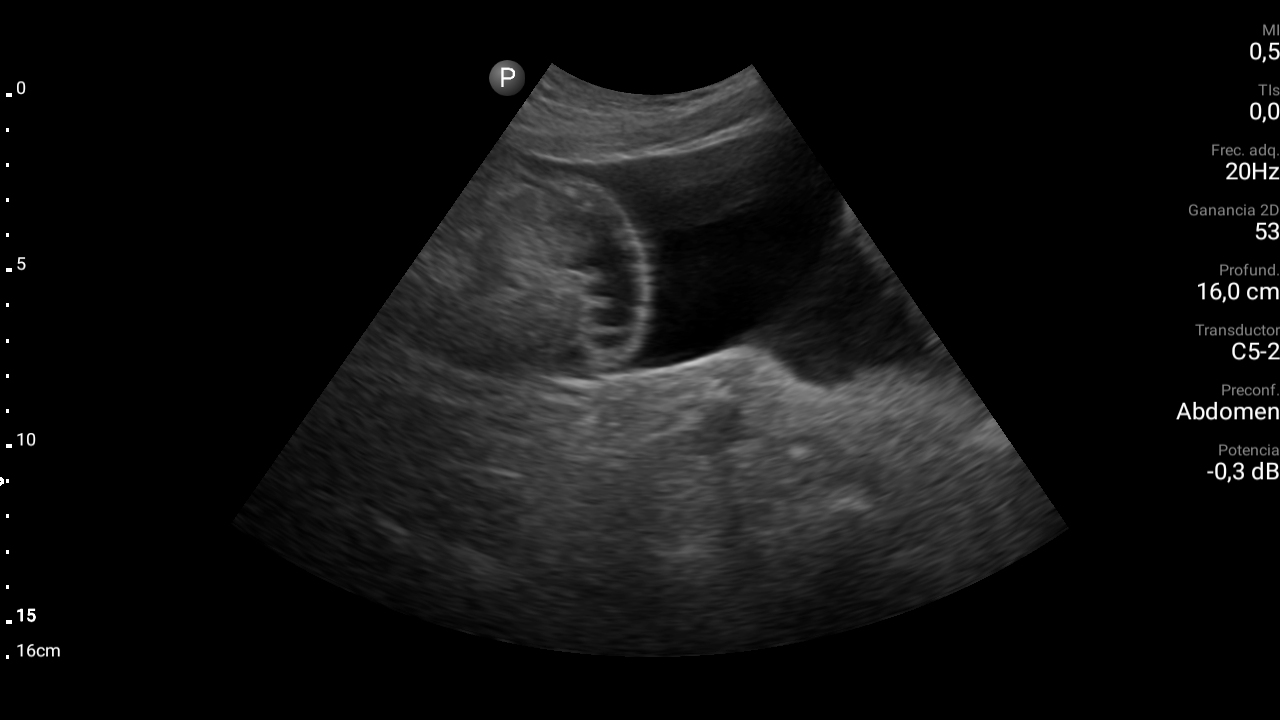

Presencia de ascitis perihepática, periesplénica. En la pelvis se visualizan asas intestinales con aspecto congestivo.

Hígado parcialmente visualizado esteatósico sin lesiones focales.

Derrame pleural bilateral moderado.